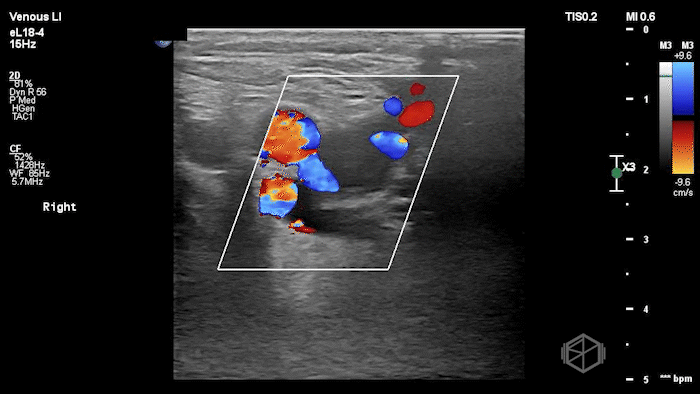

A lower extremity DVT ultrasound performed by Dr. Koutsounadis demonstrated the following:

The POCUS shows a right common femoral vein thrombus. Family members reported that the patient had previously been diagnosed with a DVT very recently and was on apixaban.

The thrombus appeared predominantly hypoechoic to nearly anechoic, making it difficult to appreciate on B-mode imaging alone. However, incomplete compressibility of the vein confirmed the presence of thrombus.

Diagnosis: Right common femoral partially occlusive DVT